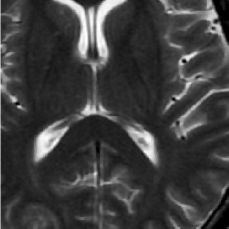

(a) Shepp-Logan phantom

Refer to caption

(b) FLAIT brain

(c) Lumbar spine

(d) Circle of Willis

Figure 2: Test Images.

We turn now to test TDIHT for high dimensional signals. We test the performance of several MRI images: the Shepp-Logan phantom, FLAIT brain image, T2 Sagittal view of the lumbar spine and the circle of Willis. The first image is of size 256×256256256256\times 256, while the other are of size 512×512512512512\times 512. They are all presented in Fig. 2.

We focus on the recovery of these images from a few number of Fourier measurements. With 𝛀𝛀{\mathbf{\Omega}} set to be the undecimated Haar transform with one level of resolution (redundancy four) and 𝐃𝐃\mathbf{D} its inverse transform, we succeed to recover the phantom image using only 181818 sampled radial lines, which is only 6.5%percent6.56.5\% of the measurements. This number is only slightly larger than the number needed for GAP, relaxed ASP (RASP) and Relaxed ACoSaMP (RACoSaMP) in [10, 38]. The advantage of TDIHT over these methods is its low complexity as it requires applying only 𝐌𝐌{\mathbf{M}} and its conjugate and 𝛀𝛀{\mathbf{\Omega}} and its inverse transform while in the other algorithms a high dimensional least squares minimization problem should be solved. Note also that for AIHT and RAHTP the number of radial lines needed for recovery is 353535 and for IHT (with the decimated Haar operator with one level of resolution) we need more than 505050 radial lines.